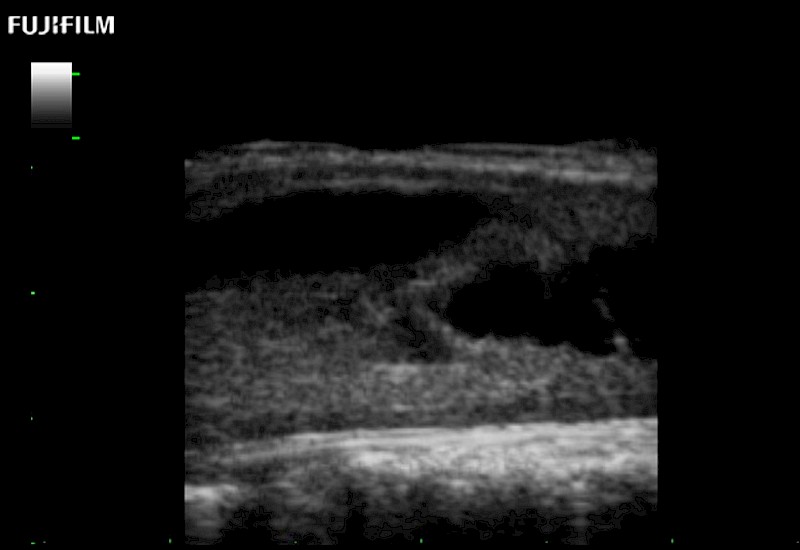

Exclusive 10mm side‐fire linear array transducer with 2.87mm diameter is ideal for real‐time visualization through and behind structures and instant, scalable definition of anatomy and vascularity including the ability to delineate and define tumor margins.

Main Specifications: